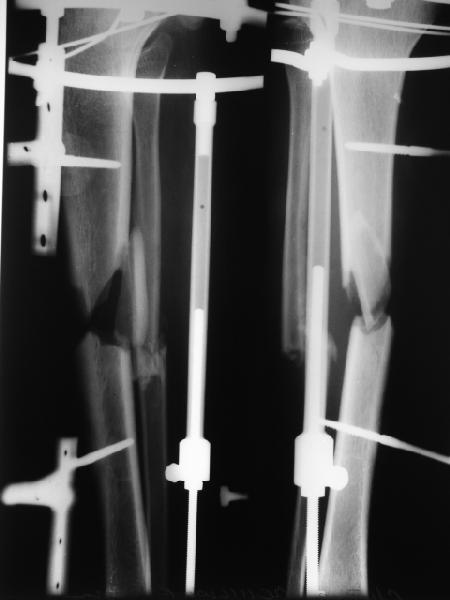

Спасибо всем коллегам за помощь! Пока готовил больного к операции БИОС, родителям "надоело" ждать и перевели парня в другой город для билокального остеосинтеза. Ещё раз всем спасибо!